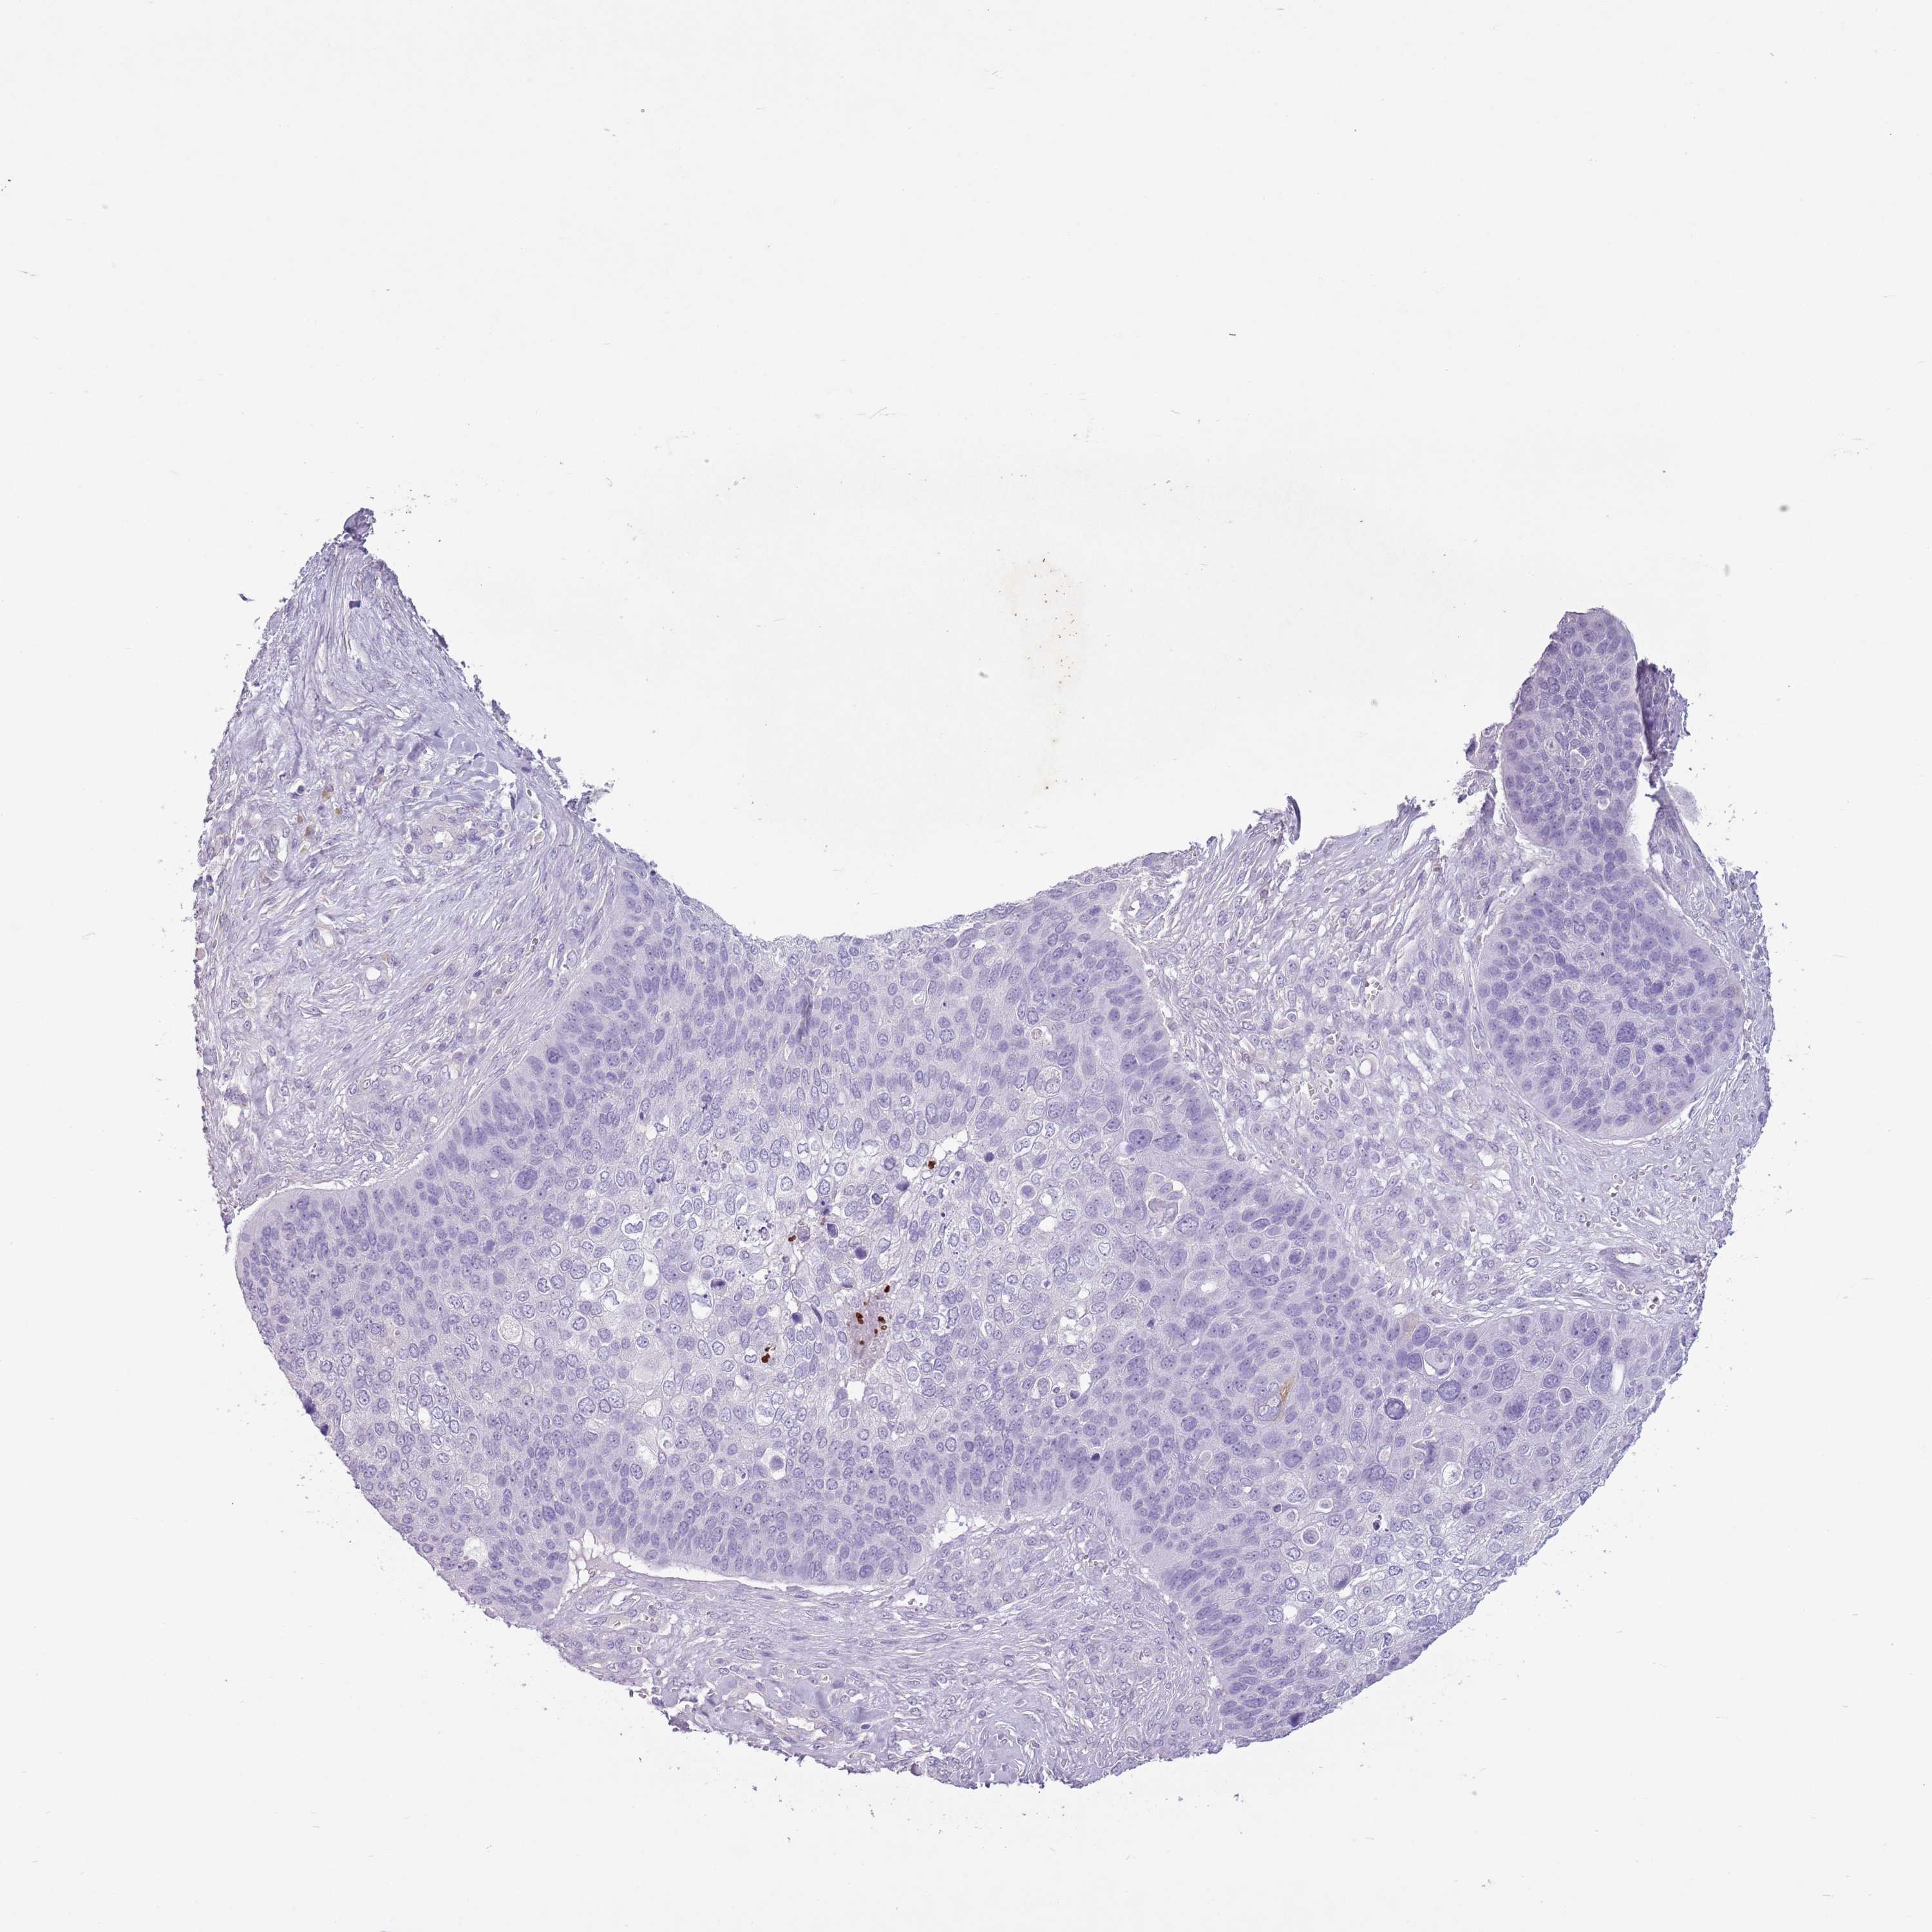

CANCER SKIN CANCER Show tissue menu

Basal cell and squamous cell cancer

SKIN CANCER - Protein expressioni

A mouse-over function shows sample information and annotation data. Click on an image to view it in a full screen mode. Samples can be filtered based on level of antibody staining by selecting one or several of the following categories: high, medium, low and not detected. The assay and annotation is described here.

Each image is clickable and will lead to virtual microscopy that enables deeper exploration of all samples and also displays staining intensity scores, fraction scores and subcellular localization as well as patient and tissue information for each sample.

Antibody HPA046985

Basal cell carcinoma